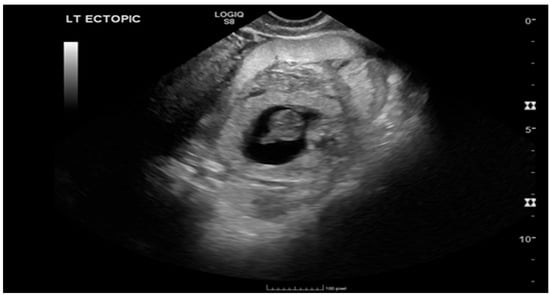

Ruptured Heterotopic Pregnancy: Laparoscopic Management, Preserving Intrauterine Viability

Pregnancy (HP), defined as the coexistence of intrauterine and ectopic gestations, is a rare condition, especially in spontaneous conception, but it is a life-threatening obstetric emergency when rupture occurs, with a reported maternal mortality rate of 0.03%. Diagnosis is often delayed because confirmation of an intrauterine pregnancy can mask clinical signs of a concurrent ectopic gestation. Early recognition and prompt surgical intervention are therefore critical to maternal safety and preservation of intrauterine viability. This case highlights the diagnostic challenges and successful management of a spontaneous ruptured heterotopic pregnancy. Case presentation: A 34-year-old Middle Eastern woman, gravida 4, with a spontaneous conception, presented with sudden severe lower abdominal pain and signs of acute hemoperitoneum (hypotension, tachycardia, and marked peritoneal signs). Transvaginal ultrasound demonstrated a viable intrauterine pregnancy at 9 weeks 4 days gestation, together with a ruptured left tubal ectopic pregnancy of similar gestational age. The patient underwent urgent laparoscopic left salpingectomy with evacuation of approximately 1200 mL of intraperitoneal blood and clots. Postoperatively, she developed significant anemia (hemoglobin drop from 11.2 g/dL on admission to 6.5 g/dL) requiring transfusion of four units of packed red blood cells. Serial ultrasonographic follow-up confirmed ongoing viability of the intrauterine pregnancy, which ultimately resulted in a live birth at term. Progressive resolution of the postoperative pelvic hematoma was also noted. Conclusions: Ruptured heterotopic pregnancy remains a diagnostic and therapeutic challenge. This case, along with a synthesis of the contemporary literature, demonstrates that a high clinical index of suspicion, timely ultrasound diagnosis, and immediate minimally invasive surgical management are paramount. Furthermore, rigorous postoperative monitoring and resuscitation, including targeted transfusion, are essential to achieve maternal stabilization while allowing continuation of a viable intrauterine pregnancy, with reported live birth rates exceeding 70% following timely intervention. Full article